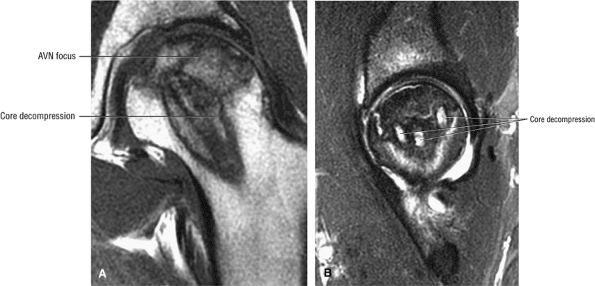

FIGURE 3.88 ● Post-core decompression for an ischemic focus with associated subchondral fracture without femoral head collapse. Arthroscopy has been performed for stage IV or post-collapse patients who are also candidates for osteotomy or vascularized graft. Delamination of articular cartilage is treated with débridement and core decompression, although improvement may be limited. (A) Coronal T1-weighted image. (B) Sagittal FS PD FSE image.

FIGURE 3.89 ● Post-core decompression for pain reduction and to delay femoral head collapse in a separate case. A fibular strut graft can also be used to prevent femoral head collapse. (A) Coronal T1-weighted image. (B) Coronal FS PD FSE image.